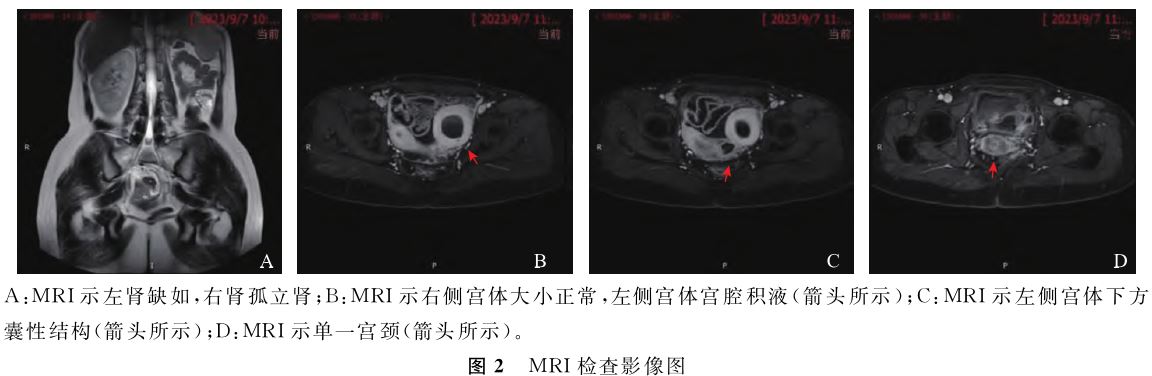

可能。泌尿系超声提示:左肾未探及,右肾代偿性增大。下腹部+盆腔MRI示:(1)右侧单角子宫伴宫颈水平相连伴有功能性子宫内膜的左侧残角子宫;左侧宫腔下方囊状影,考虑为左侧阴道阻塞积血可能性大;(2)右肾孤立肾(图2)。